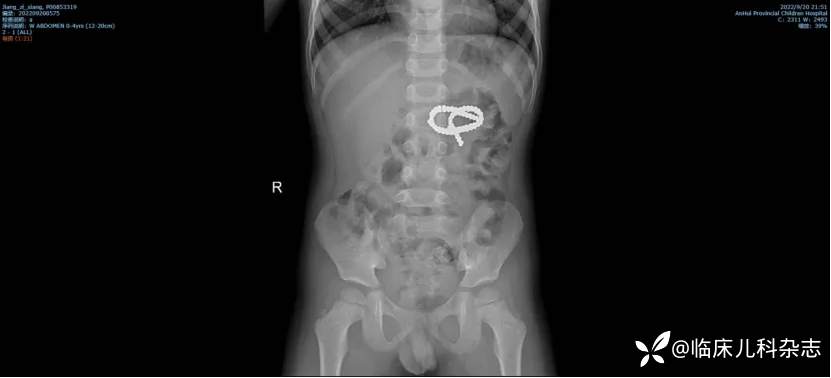

41 例磁力珠误食患儿中,22 例出现消化道穿孔,部分需手术造瘘;